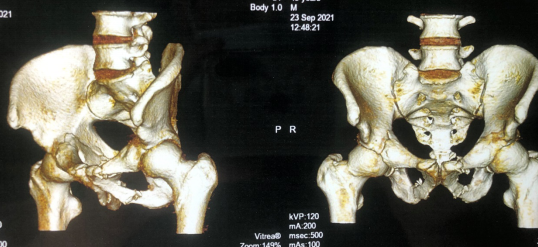

但是刘大柱的右胫腓骨粉碎骨折、右侧髋臼横行骨折及骨盆耻骨支骨折,如果不进行手术可能以后都无法再次站立。患者及家属手术意愿强烈,随后转入创伤骨科。待刘大柱身体稍作恢复,进行后续手术治疗。

考虑到刘大柱的伤情比较严重,并且才做完头部手术不久,如果进行常规开放性手术,切口暴露大、术中出血多,复位过程的监测和复位后固定难度均较大而且难以实现精准复位;其次,术中定位不准确,手术操作极易损伤血管神经,反复透视辐射大,易出现二次损伤等风险。

创伤骨科夏建军副主任医师和手术团队经过讨论,决定给患者进行天玑骨科机器人辅助下右髋臼、骨盆骨折闭合复位内固定术。